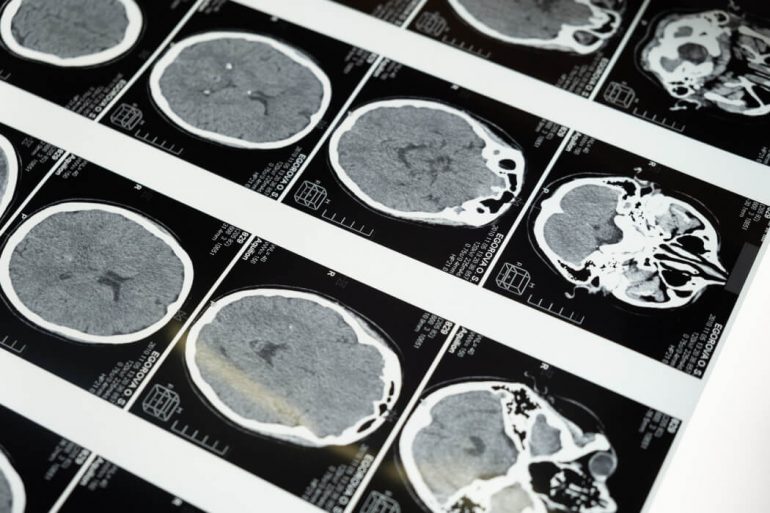

PocketHealth’s app allows patients to access, share, and store their own medical image records like X-rays, ultrasounds, CT scans, and MRIs securely using “bank-level encryption technology.” The company, which describes itself as “the world’s first patient-centric image sharing platform,” was founded in 2016 by Citigroup alum Rishi Nayyar and his brother, former Google software engineer Harsh Nayyar.

PocketHealth’s plans also involve moving beyond just facilitating access to medical records—the startup also wants to help patients understand them. Earlier this month, the company launched Report Reader, a new tool that enables its users to easily surface “patient-friendly terminology” inside of their radiology reports.